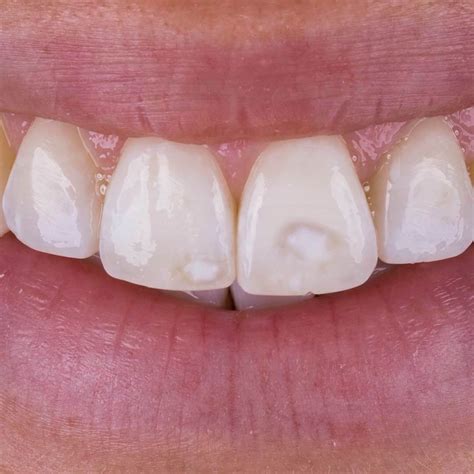

- Hipocalcificación: Hay una alteración en la calidad del esmalte de modo que se ve más opaco, de manera más localizada o difusa.

- Fluorosis: Es un tipo de hipoplasia producida por una ingesta excesiva y prolongada de flúor. Se puede presentar como manchas de aspecto moteado, también puede haber pérdida de esmalte, y al quedar expuesta la dentina, se facilita la tinción del diente con sustancias que se depositan sobre él.